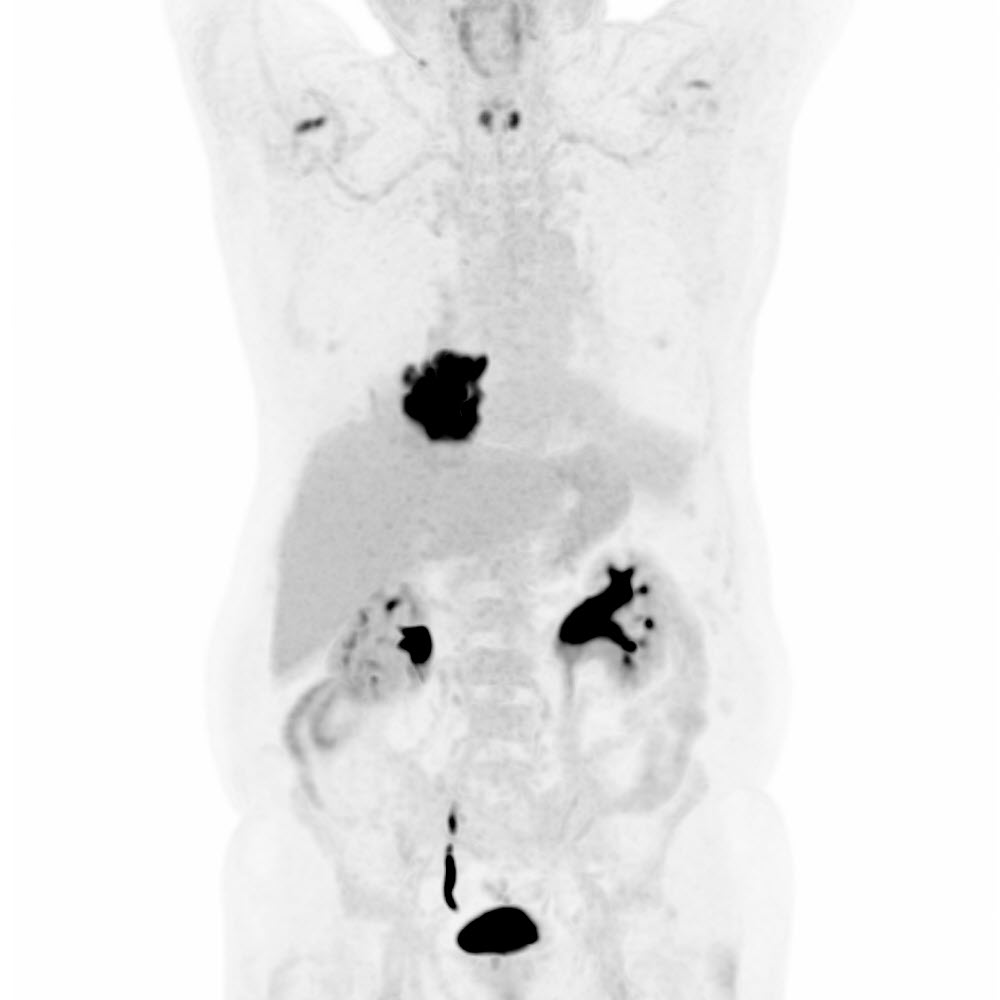

NSCLC (Plattenepithelkarzinom). Status nach neoadjuvanter Chemo-/Immuntherapie. Verlaufskontrolle. Ansprechen?

PET/CT des Körperstammes

mit F-18-FDG

- Deutliches Therapie-Ansprechen mit vollständig rückläufiger Stoffwechselaktivität und Grösse des NSCLC rechts basal.

- Rückläufiger Pleuraerguss rechts.

- Keine Metastasen.

FDG-PET/CT

nach Therapie